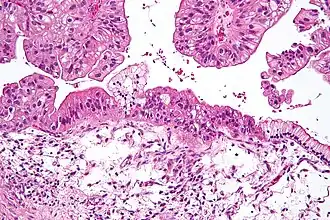

![]() Муцинозная опухоль яичника низкого потенциала злокачественности. Среднее увеличение, окраска гематоксилин-эозином. | |